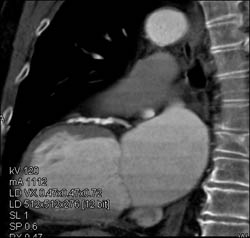

Diseased LAD